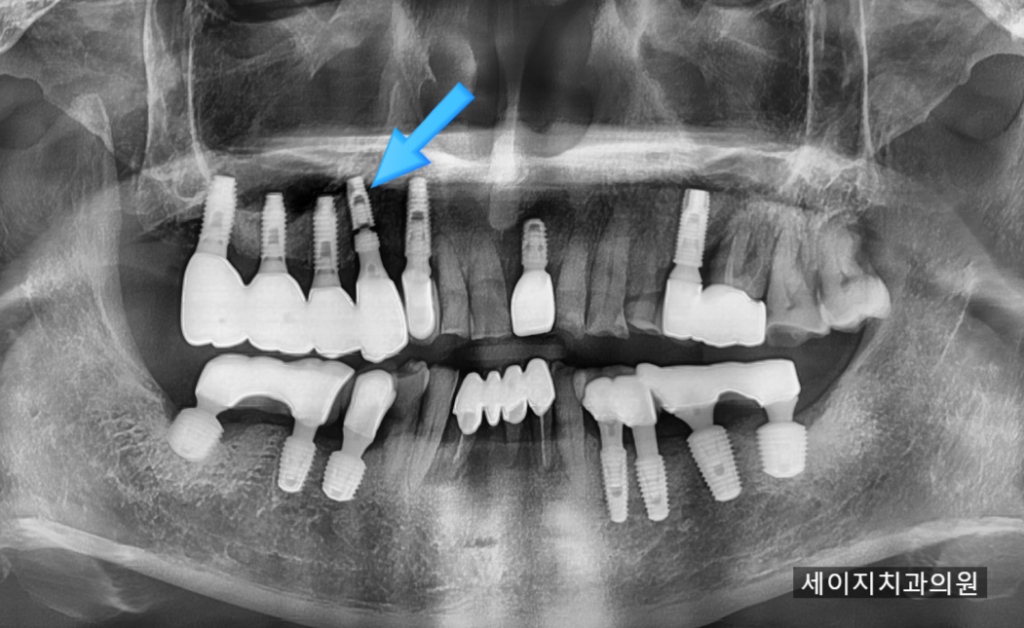

24. 12. 09

엑스레이를 통해 먼저 환자분이 말씀을 주셨던 곳을 확인해 보았습니다. 불행하게도 분리된 임플란트가 관찰이 됩니다.